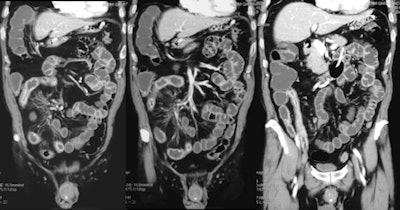

High-quality CT images of the abdomen and pelvis can be acquired by using the latest iterative reconstruction techniques at an ultralow dose (1.3 ± 0.8 mSv) in patients with Crohn's disease, enabling the detection of most complications, according to Irish researchers.

Iterative reconstruction, a noise-efficient reconstruction algorithm, minimizes the impact of increased image noise in images acquired at low doses, improving image acceptability. This technique allows radiation dose reduction by reducing image noise compared with the standard FBP technique. When it is used in low-dose CT scanning in patient and phantom studies, a radiation dose reduction of 32% to 65% is possible with significantly less noise and preserved low-contrast resolution and image quality, according to O'Neill.

Typical indications for CT in Crohn's disease include establishing the initial diagnosis and quantification of disease distribution, extent, and activity, as well as assessment for complications such as active enterocolitis, abscess, fistula, stricture, and lymphadenopathy.